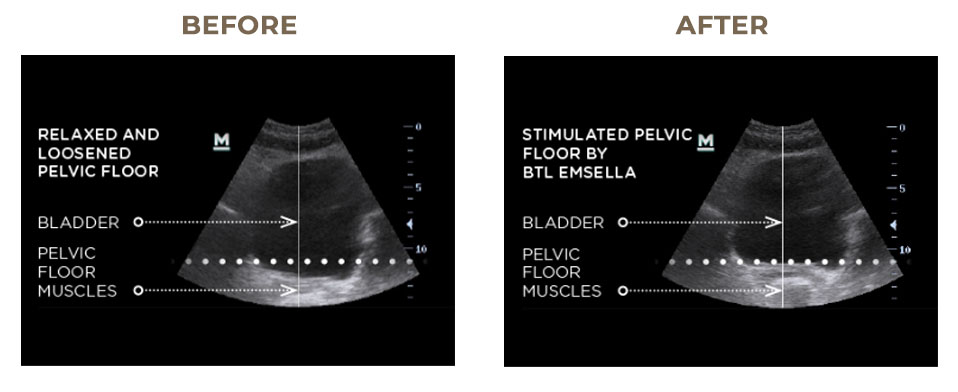

EMSELLA makes strengthening your pelvic floor effortless. You simply sit fully clothed in the EMSELLA chair while gentle electromagnetic energy does the work for you. Using HIFEM® technology, EMSELLA induces thousands of Kegel-like pelvic floor muscle contractions in a single session, far more than you could ever achieve on your own.

These deep contractions re-educate and strengthen weak pelvic floor muscles, helping to restore neuromuscular control and improve urinary incontinence in both men and women. With each session, the pelvic floor grows stronger, providing better support for the bladder and a noticeable boost in confidence and control, all without effort, surgery, or downtime.